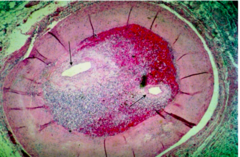

Nutmeg pattern

-seen in congested liver -grossly congested areas that are dark red, and alternate with normal brown liver